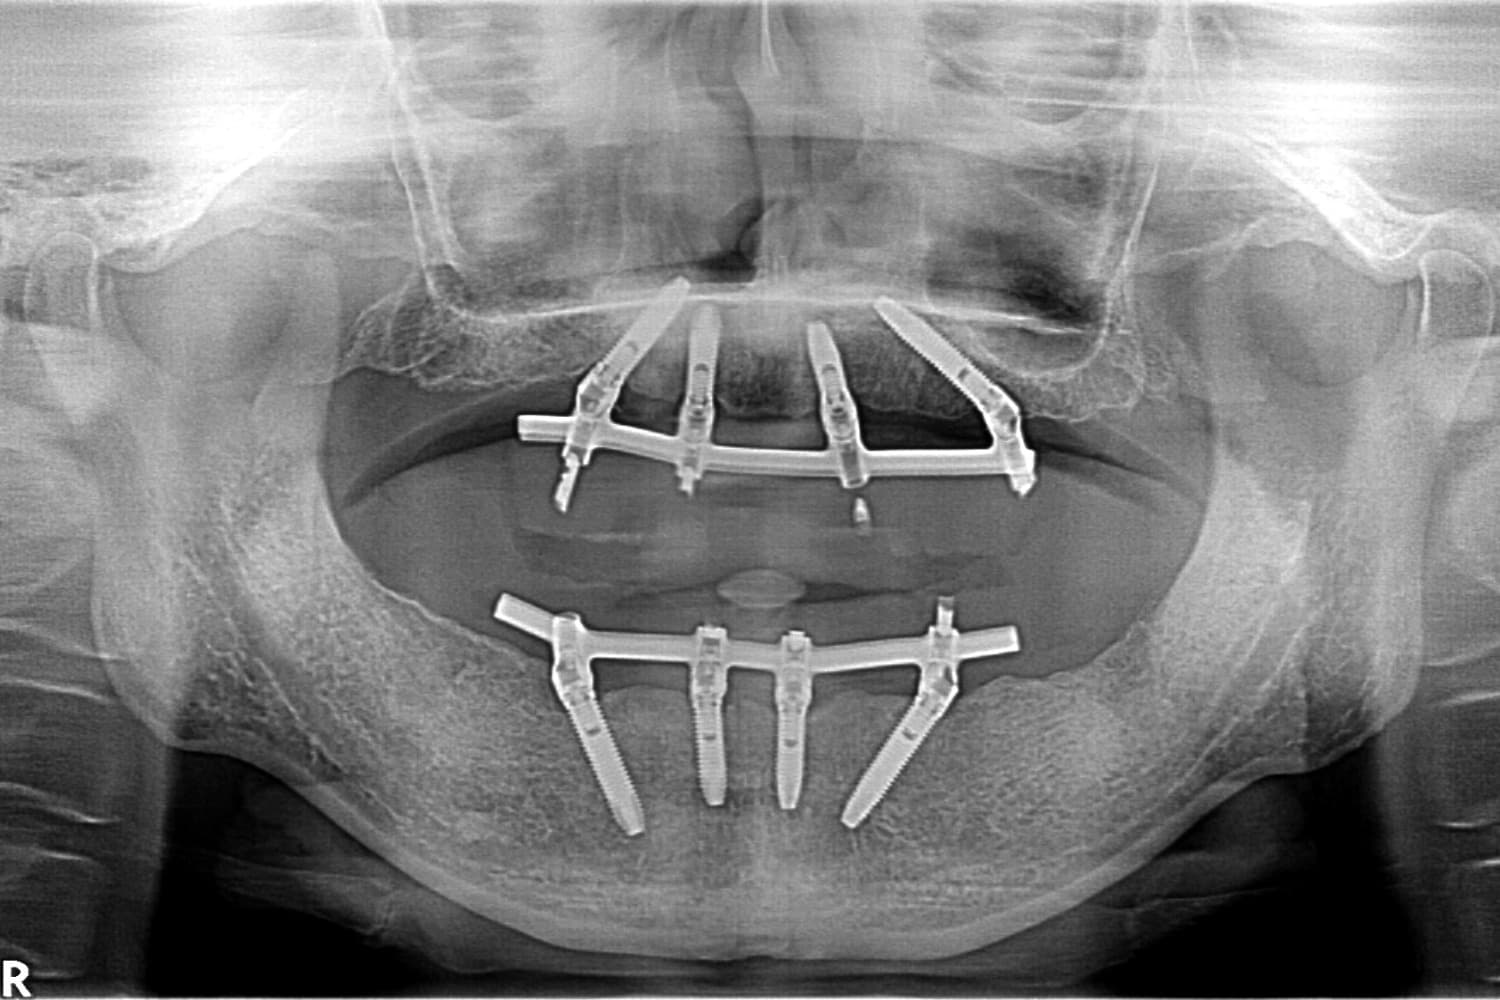

全歯のインプラント治療(50代/男性)

After

オールオン4

年齢

50代

性別

男性

主訴

他院で総義歯を入れたが、噛むと上の義歯が落ちて使えない。インプラント相談希望。

治療期間

10カ月

治療回数

12回

費用

6,000,000円+骨造成代

副作用・リスク

メインテナンスが出来ていないとインプラント周囲炎になる。よく噛めるため、上部構造が使用していくうちに破損することがある。